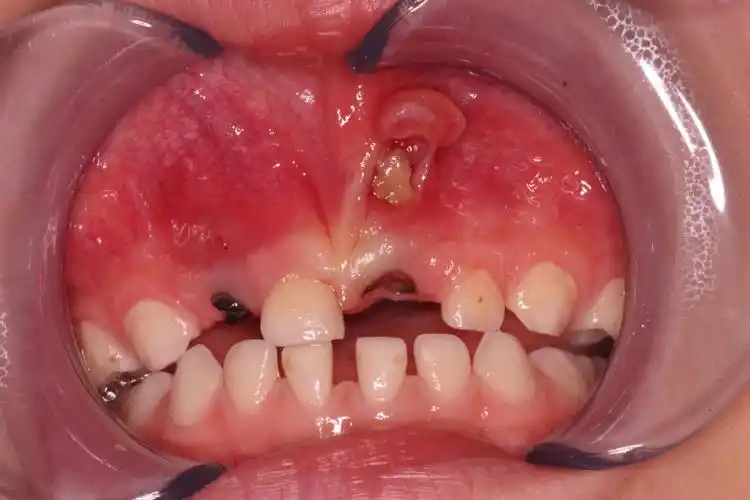

乳牙早晚都是要换的,只要不疼,乳牙龋齿不治也行吧?